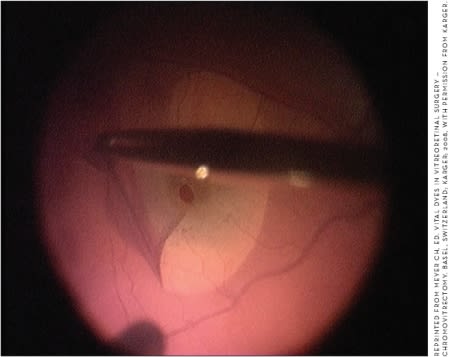

Indocyanine green is a fluorescent cyanine dye that binds to plasma protein, which keeps it localized in the blood vessels. Because of this property, ICG has been used in ophthalmology as an alternative angiographic dye to fluorescein since the 1950s.1 In 2000, surgeons began using it as a stain in macular hole surgery.2 Going on the assumption that macular holes are more likely to close if there have been deeper dissections, and because peeling the ILM results in such dissections,3,18 ICG has been applied to the ILM to assist peeling by increasing visualization (Figure 1).

Figure 1. Membrane peel with ICG in macular hole surgery.